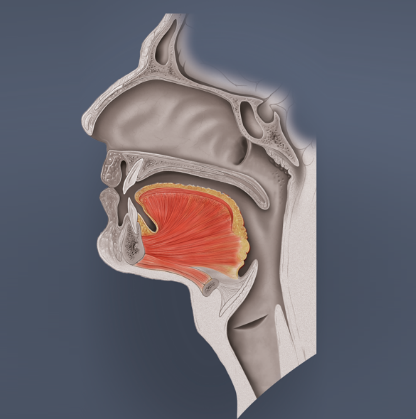

- Zunge (engl. tongue)

Die Zunge spielt eine wichtige Rolle beim Druckausgleich, denn sie kann die Mundhöhle an verschiedenen Positionen in einen vorderen und hinteren Bereich unterteilen. Dies wird später bei den „Stimmübungen“ klarer.

- Zunge

Die Zunge kann den Mundraum in den vorderen und hinteren Mundraum unterteilen. Das ist an drei unterschiedlichen Stellen möglich und zwar durch das Sprechen der Buchstaben T (Verschluss vorne knapp hinter den oberen Zähnen), CA (Verschluss mittig) oder des arabisch gehauchten H (Verschluss hinten – geht auch mit CH)

Der sogenannte T-Verschluss kann auch mit den Buchstaben D oder N durchgeführt werden.

Beim Tauchen kann der Mund – bedingt durch das Mundstück des Atemreglers – nicht dicht verschlossen werden. Insofern wird beim Druckausgleich mittels Valsalva-Manöver immer eine der drei möglichen Verschlussarten (T, CA oder H) durch die Zunge benutzt um die Luft aus der Lunge vom hinteren Mundraum weiter in den Nasenraum zu drücken.